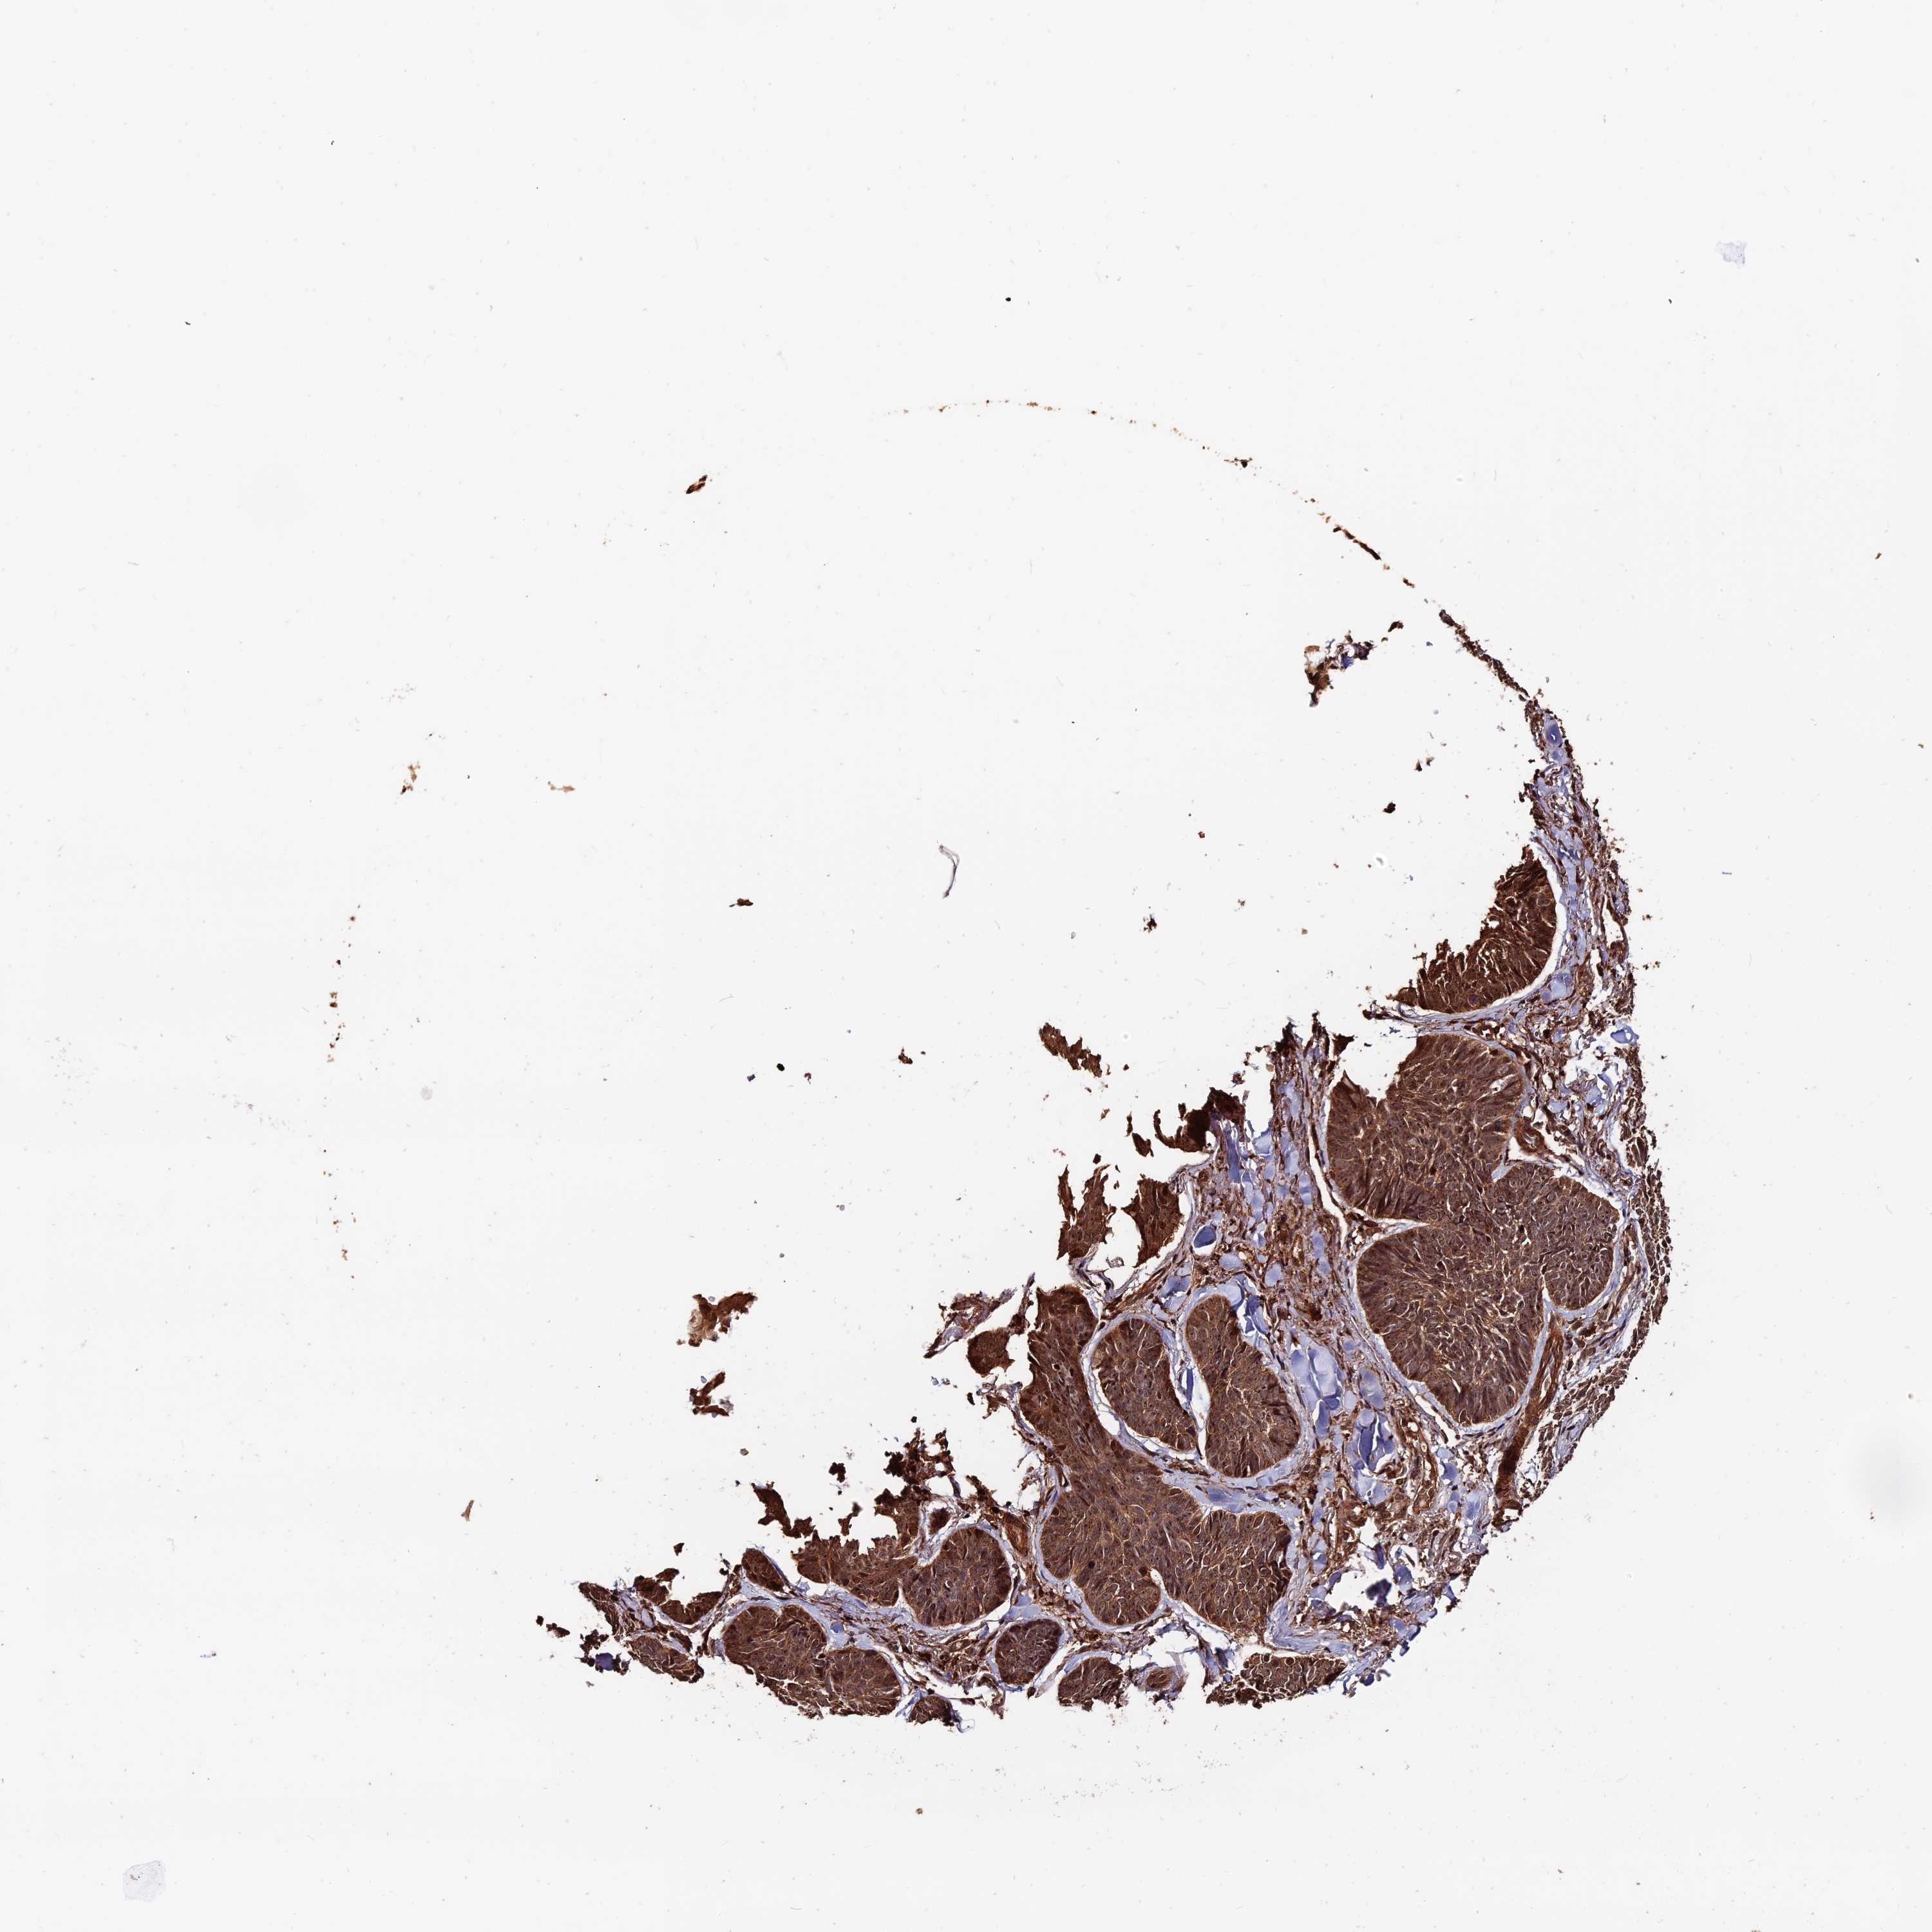

SKIN CANCER - Protein expressioni

A mouse-over function shows sample information and annotation data. Click on an image to view it in a full screen mode. Samples can be filtered based on level of antibody staining by selecting one or several of the following categories: high, medium, low and not detected. The assay and annotation is described here.

Antibody stainingi

Antibody staining in the annotated cell types in the current human tissue is reported as not detected, low, medium, or high, based on conventional immunohistochemistry profiling in selected tissues. This score is based on the combination of the staining intensity and fraction of stained cells.

Each image is clickable and will lead to virtual microscopy that enables deeper exploration of all samples and also displays staining intensity scores, fraction scores and subcellular localization as well as patient and tissue information for each sample.

Antibody HPA040390

Antibody CAB002611

Staining

High

Medium

Low

Not detected

Intensity

Strong

Moderate

Weak

Negative

Quantity

>75%

75%-25%

<25%

None

Location

Nuclear

Cytoplasmic/membranous

Cytoplasmic/membranous,nuclear

Basal cell carcinoma